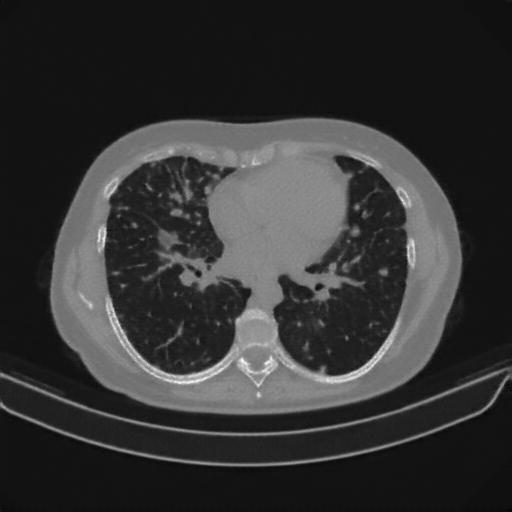

Generated VENOUS CT scan (A→B translation)

Lung window (WL -600, WW 1500 β†’ Low βˆ’1350, High +150)

Mediastinum window (WL 40, WW 400 β†’ Low βˆ’160, High +240)

Targeted Slice 70 - Lung Window Analysis (Generated vs Real Venous)

0.752

Lung SSIM

110.9

Lung RMSE

46.5

Lung MAE

Average Lung Window Metrics Across All Slices (133 slices) - Generated vs Real Venous

0.749

Lung SSIM (Avg)

109.7

Lung RMSE (Avg)

44.6

Lung MAE (Avg)